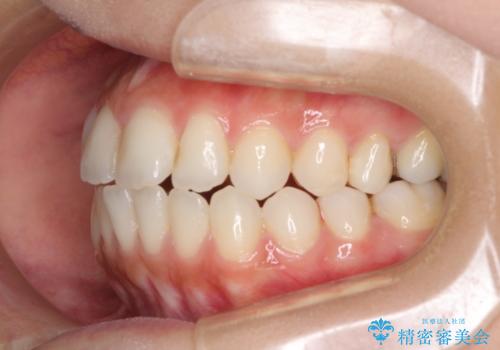

- オープンバイトのため、話しているときの見た目が気になるとのことで来院された患者様です。

下顎骨は左側にシフトしており、咬み合ったときには奥歯と前歯の一部しか接触していない状態でした。

骨格的な左右差は歯列矯正は改善できないため、上下歯列が全体的に接触することをゴールとしてインビザラインにて矯正治療を行うこととしました。

前歯のデコボコの解消と並行して上下の奥歯を圧下させるようにすることで、前歯を接触させるように計画しました。

上下の隙間に舌が入り込むことがオープンバイトの原因であったため、舌の筋肉のトレーニングも並行して行い、後戻りの抑制を図りました。